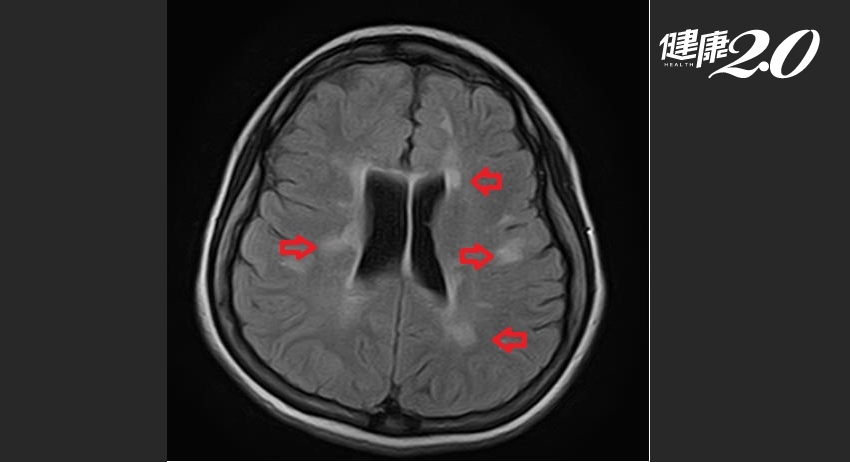

鄧浩文指出,在沒有三高或吸菸的年輕人身上,出現類似中風的局部神經症狀,通常非單純疾病,需要高度懷疑為腦部疾病,尤其可能是腦幹病變。少女經腦部核磁共振檢查,發現在右側的腦幹與小腦交界以及腦室周遭有多處疑似去髓鞘病灶的卵圓形斑塊,經過其他檢查,包括腦脊髓液檢查排除其他疾病後,確診是罹患多發性硬化症。

▲ 少女患者的右側腦幹與小腦交界、腦室周遭有多處卵圓形斑塊。